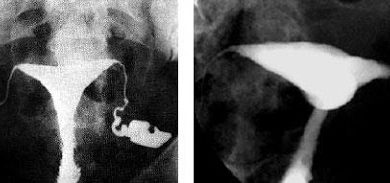

HSG, rahim ve tüplerin radyo-opak madde (boyalı madde) kullanılarak görüntülendiği bir radyolojik yöntemdir. Kadın-Doğum hekiminin radyoloji ünitelerinde uygulamasını yaptığı bu…

Bu muayene çoğu zaman, rahmin (uterus) ve fallop tüplerinin daha yakından incelenmesi amacıyla yapılır. Histerosalpingografi, rahmin (histero) ve fallop tüplerinin…